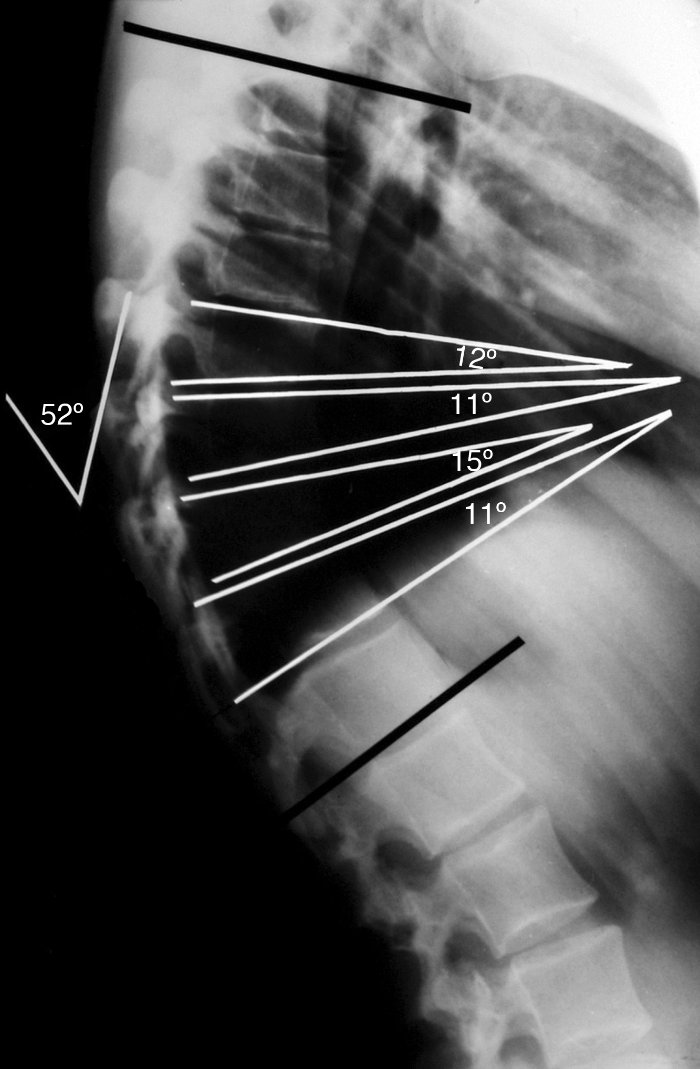

Κατά τον ακτινολογικό έλεγχο παρατηρούνται:

- Γωνία Cobb > 45 μοίρες, η μέτρηση γίνεται από τον Θ3 έως τον Θ12 σπόνδυλο (κάποιες φορές πάντως μπορεί να υπάρχει Scheuermann και με γωνία <45 μοίρες)

- Σφηνοειδής παραμόρφωση τουλάχιστον 3 συνεχόμενων σπονδύλων. Η σφηνοειδής παραμόρφωση των σπονδύλων θα πρέπει να είναι το λιγότερο 5 μοίρες για τον καθένα